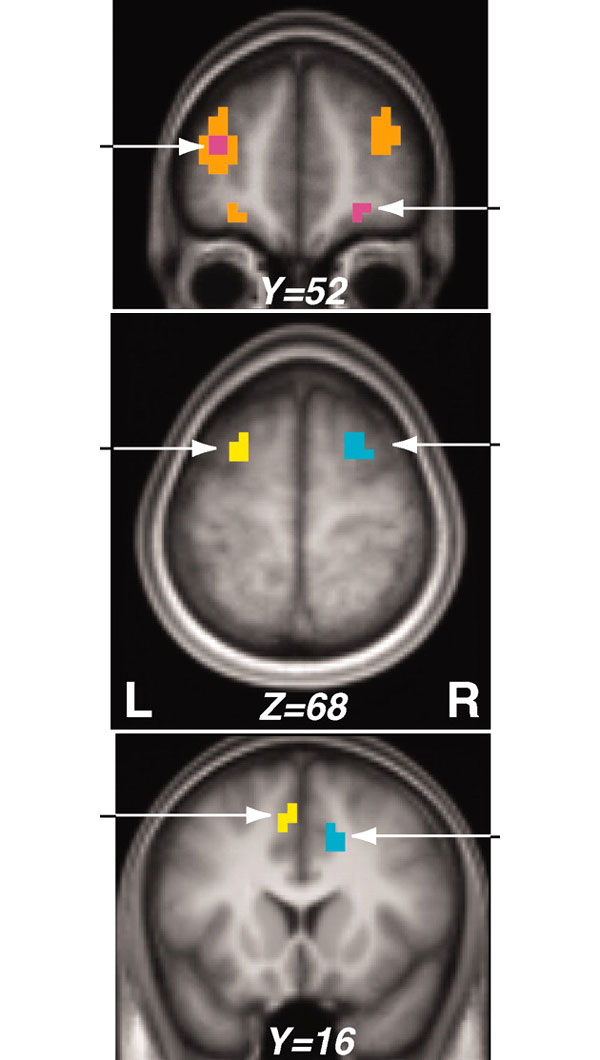

В медиальной фронтальной коре (MFC) обнаружились две области (dACC и PMC, см. рисунки), избирательно кодирующие информацию о первой и второй награде. В ситуации «переключение», когда нужно было помнить только об одной награде, эти области возбуждались примерно одинаково слева и справа. В ситуации «разделение» левое полушарие кодировало первую («основную») награду, правое — вторую («дополнительную»).

Таким образом, когда человек имеет в голове только одну цель, информация об ожидаемой награде отображается симметрично в левой и правой MFC. Когда же приходится иметь в виду сразу две цели, происходит разделение функций между полушариями: левая MFC отображает первую мотивацию, правая — вторую. Что касается APC, «высшей аналитической инстанции», то она интегрирует информацию об обеих одновременно преследуемых целях.